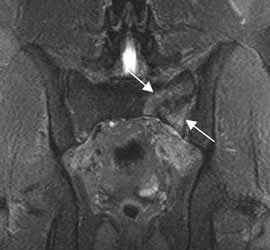

Fig 57 B. Fractura de stress.

RM coronal en STIR: Edema en el alerón del sacro izquierdo, por fractura de stress.